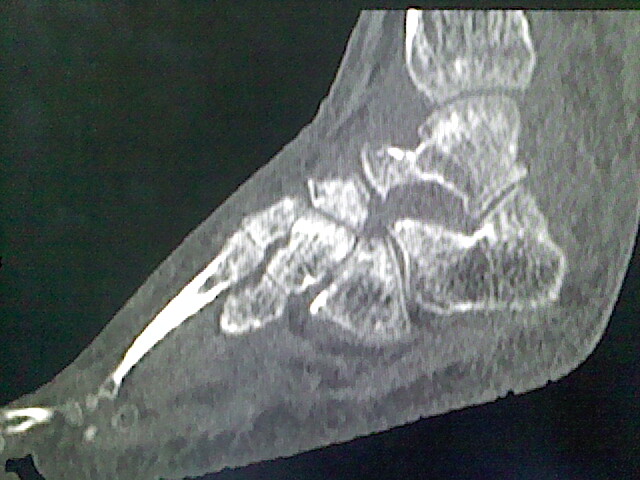

标题: CT16814:男,76岁,左小腿疼痛,不能站立 大家给看看 [打印本页]

男,76岁,左小腿疼痛,不能站立

本例骨质改变主要表现为滑膜或韧带区的骨侵蚀融解(胫腓联合区骨质破坏无硬化边),距骨后部骨质破坏区有硬化边及死骨样改变.所以,本例考虑关节结核可能性大,绒毛膜结节性滑膜炎多发于中年,且极少见于膝髋以外的关节,骨质硬坏也以压陷吸收为主,有明显的硬化边,骨膜增生呈结节状(可以mr鉴别),所以本例暂除外.

另不除外可引起相似表现的其他炎症如布氏杆菌性关节炎等